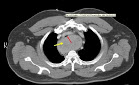

- Although rare, thyroid glands within the mediastinum may exist without connection to the normal cervical orthotopic gland:

- Such purely isolated mediastinal goiters represent only 0.2% to 3% of all goiters requiring surgical treatment

- Blood supply of the isolated mediastinal goiter may be through purely mediastinal arteries (including the aorta, subclavian, internal mammary, thyrocervical trunk, and innominate) and veins: